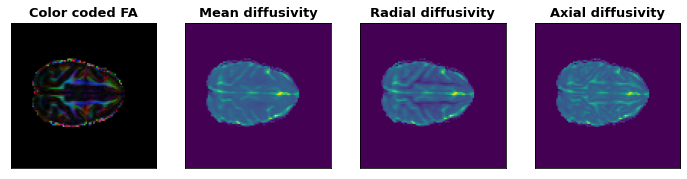

DTI results

This project started with medical imaging data format, then preprocessed the diffusion weighted images, which includes MP-PCA denoising, FSL TOPUP distortion correction and head movement correction. After this, DTI images were reconstructed from these preprocessed images successfully. Additionally, a dataset for left and right hemispheres classification was generated from these preprocessed images. By using the KNN method, classification accuracy of 92% was reached. As a starter, I will continue this project in the future. Soon, self-made models, instead of DTI model, will be used to reconstruct diffusion images. After that, I would like to use machine learning methods to classify potential changes of brain microstructures.